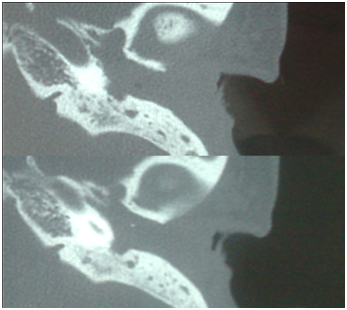

CT scan temporal bone shows left mastoid cells occupied by soft tissue density suggestive of chronic disease and EAC with the presence of soft tissue density, the tympanic cavity is also occupied by same soft tissue density that erodes its walls and no ossicular chain is observed. Carotid artery, jugular fossa, semicircular canals, cochlea and other structures unchanged (Figure 2). The right ear is normal. The skull MRI shows a hypointense occupying the left EAC on T1 that becomes hyper intense in T2 sequence and shows a heterogeneous enhancement when contrast is applied (Figure 3).

Figure 2A Coronal CT scan with tumor in the EAC and tympanic cavity; lysis of the tympanic membrane and oscicular chain.

Figure 2B Coronal CT Scan with erosion of the posterior wall of the EAC.